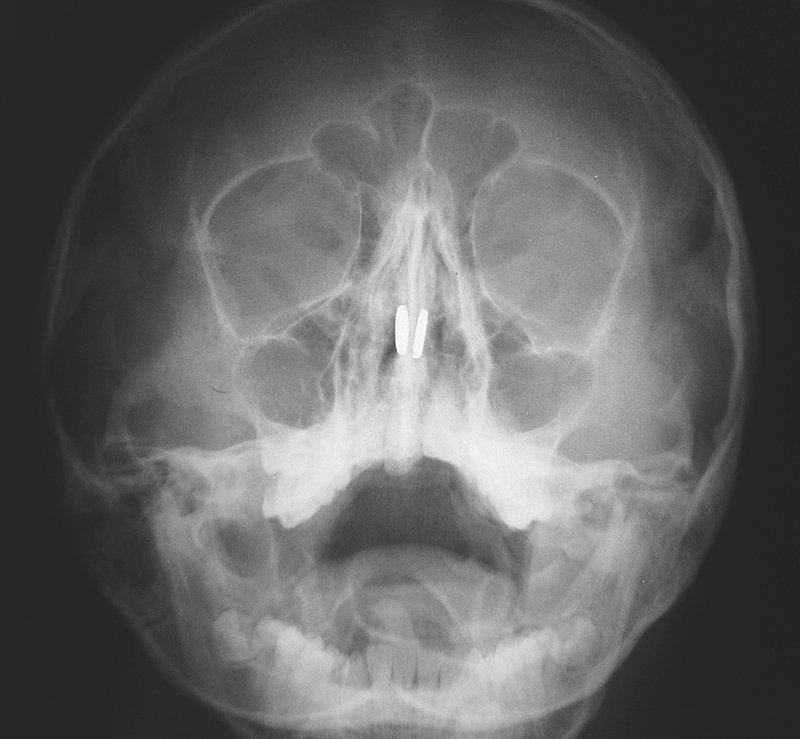

An 11-year-old boy was brought to the emergency department with epistaxis and severe nasal pain.

What is the likely diagnosis?

Nasal polyps

Nasal septum fracture

Pills in the nasal cavity

Coins in the nasal cavity

Button magnets in the nasal cavity Image

Answer

Button magnets in the nasal cavity

Children commonly insert objects into body cavities.

The discovery of attracting magnets in the nasal cavity necessitates emergency removal because they can compress the mucosa of the nasal septum, leading to necrosis and septal perforation

Read 6 tweets